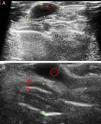

Given that basal cell carcinomas have fairly characteristic sonographic features, images can be of great value in the differential diagnosis of doubtful lesions, for example for distinguishing between pigmented basal cell carcinoma (Fig. 3A) and nodular melanoma. Ultrasound imaging has also been used to establish the perimeter of a lesion, in the sense that it allows the operator to discern whether the carcinoma has invaded nose or ear cartilage (Fig. 3B).

A, Typical ultrasound image of a basal cell carcinoma in the leg: the lesion is hypoechoic, borders are well defined, and hyperechoic dots can be seen inside the carcinoma (faint red circle). B, Basal cell carcinoma after multiple regressions in the left wing of the nose. The basal cell carcinoma (red circle), as described above, can be distinguished from nasal cartilage represented by a hypoechoic band (red bracket).